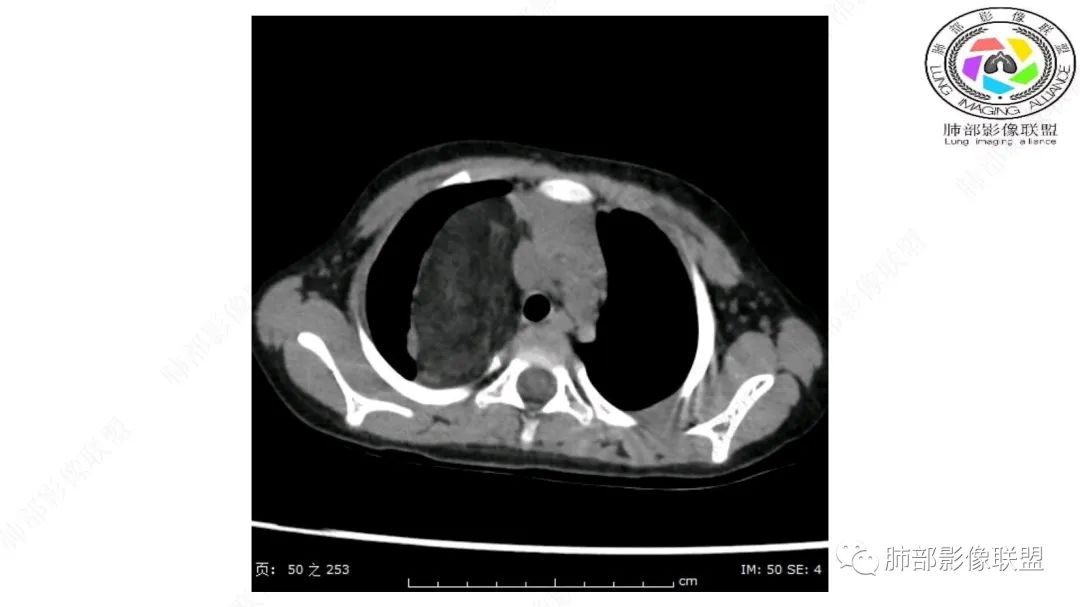

三岁小儿,右侧纵隔巨大脂肪密度肿块,肺动脉穿行其中,密度欠均匀,未见明确实性成分,纵隔脂肪母细胞瘤,冬眠瘤鉴别纵隔脂肪增多症(多弥漫对称)。

右肺门上方,位于纵隔胸膜旁见巨大肿块,脂肪为主混合密度,内见细小血管影,肿块最大长径与纵隔胸膜平行,包绕右肺上叶肺动脉,右肺上叶及纵隔结构推压,无侵蚀破坏,良性肿瘤,起源纵隔胸膜血管平滑脂脂肪瘤。

病灶属于交界区,主体位于肺内,占位效应明显,前方突入胸壁,胸腺受压变形,胸膜显示欠清楚;病灶包绕上叶肺动脉;似乎有体动脉供血。符合肺内的点:包绕上叶肺动脉分支;符合纵隔的点:前方似乎突入胸壁,与胸腺关系比较密切,但是与上腔静脉的关系提示病灶不支持纵隔来源,前纵隔的常规会将上腔静脉受压后移、外移,这是不符合的。

手术记录:见右肺上叶肿物,肿物与右肺上叶关系密切。与纵隔无粘连,逐步分离肿物,见肿物大小约6cm*5cm,边界清楚,于右肺上叶粘连,边界清楚,肿物包绕右肺上叶血管及支气管。超声刀逐步游离肿物,完整切除肿物,右肺上叶肺组织无破溃,表面无出血。

1.右上肺-纵隔交界区巨块影,主体位于右肺一侧,紧贴胸腺、头臂干、右锁骨下动脉、上腔静脉、奇静脉等,不能分离,但病灶整体边界清楚。注意上述相邻腔静脉等结构未见受压变形,纵隔亦未见明显向左推移,至少提示两点:

2.肺动脉穿行也许是肺内来源最重要支持点!

脂肪母细胞瘤由成熟程度不同的脂肪组织、纤维间隔、黏液基质、小血管丛等间质成分组成,以脂肪组织与黏液样基质为主,其影像学表现取决于上述组织成分。典型的CT和MRI表现为:前后纵隔均可发生,常见于前纵隔;肿块大小不一,直径多在3cm~7cm,密度均匀,CT值呈水样或脂肪密度,脂肪组织密度或信号为主的肿块,其内密度或信号不均匀,可见粗细不一的分隔影,且有结节、片状影,后者可呈轻中度强化;结节状肿瘤包膜完整;弥漫性者包膜不明显,常呈浸润性生长;周围结构为受压和推移改变,可有少量胸腔积液,淋巴结无增大。